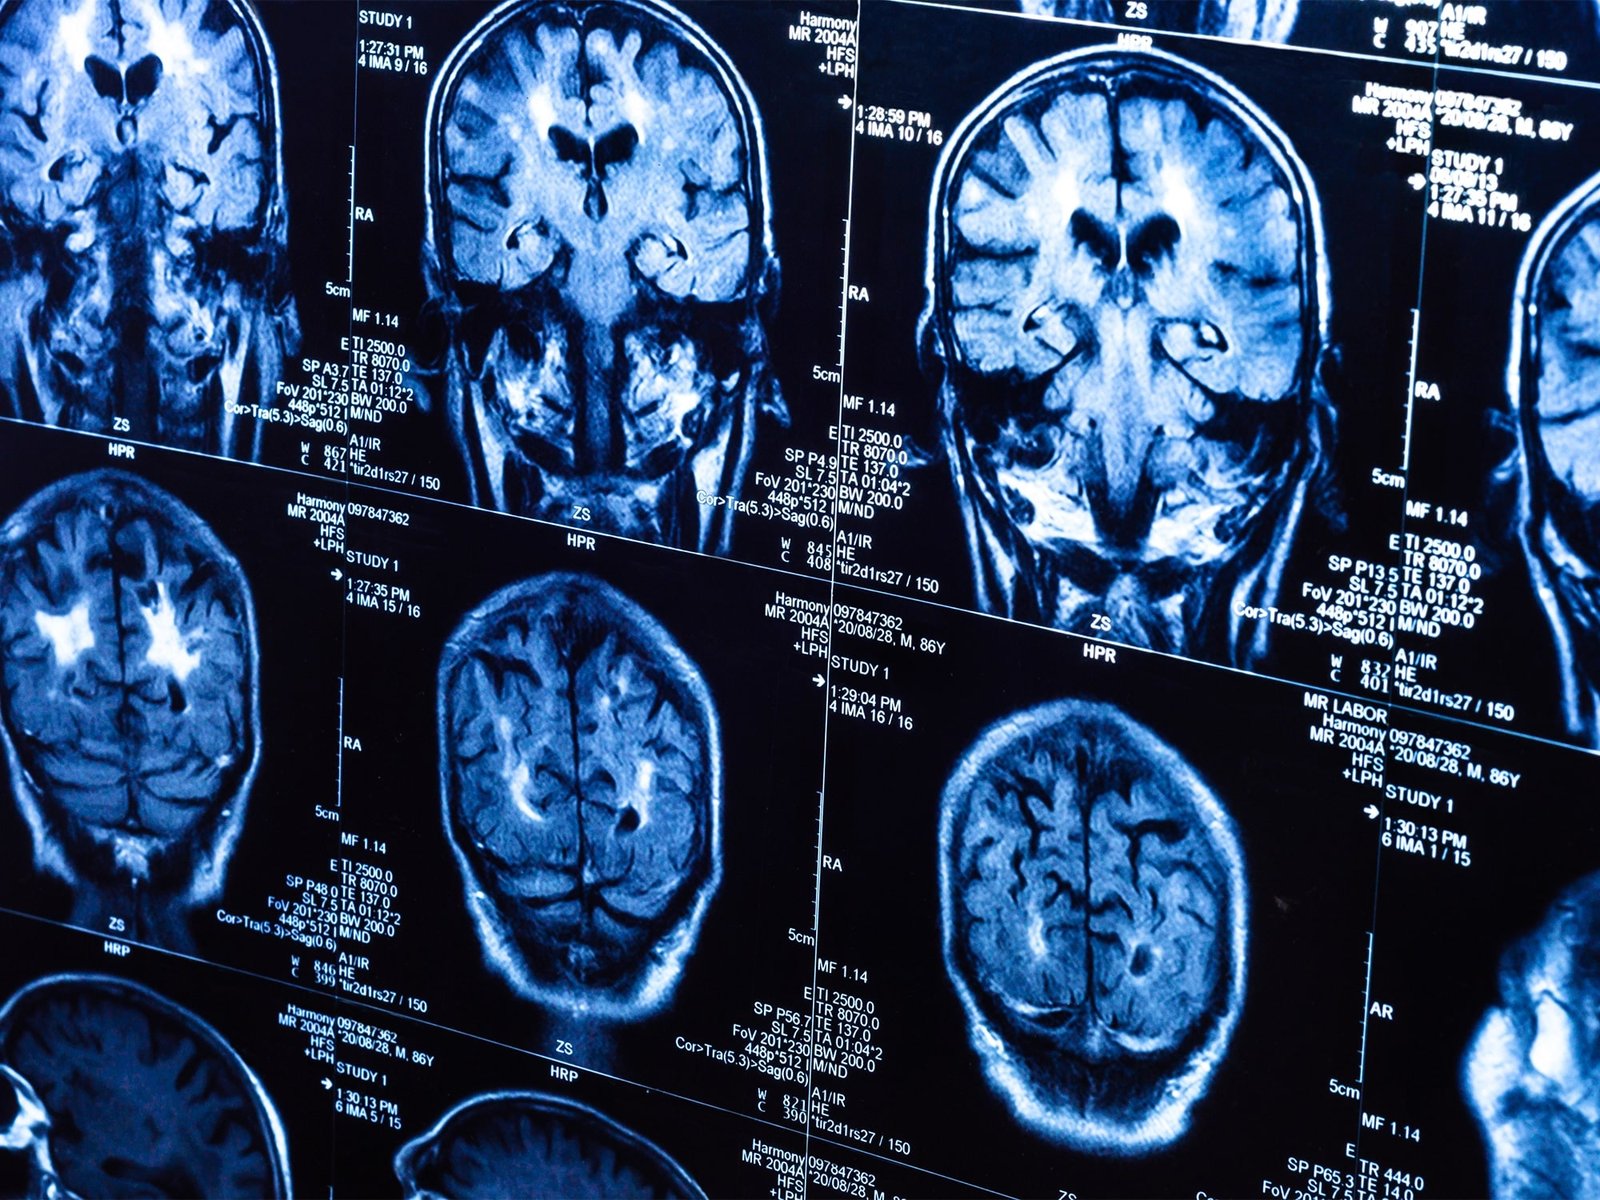

Bilim insanları, UK Biobank’ta yer alan 15 binden fazla yetişkinin verileriyle sağlıklı beyin yaşlanmasını tanıyan bir yapay zeka modeli geliştirdi.

Model, pandemiden önce tarananlarla pandemi sırasında taranan iki grubun beyin yaşlarını karşılaştırdı.

Buna göre, pandemi sürecinde insan beyninin yaşlanma hızı ortalama 5,5 ay öne çekildi.